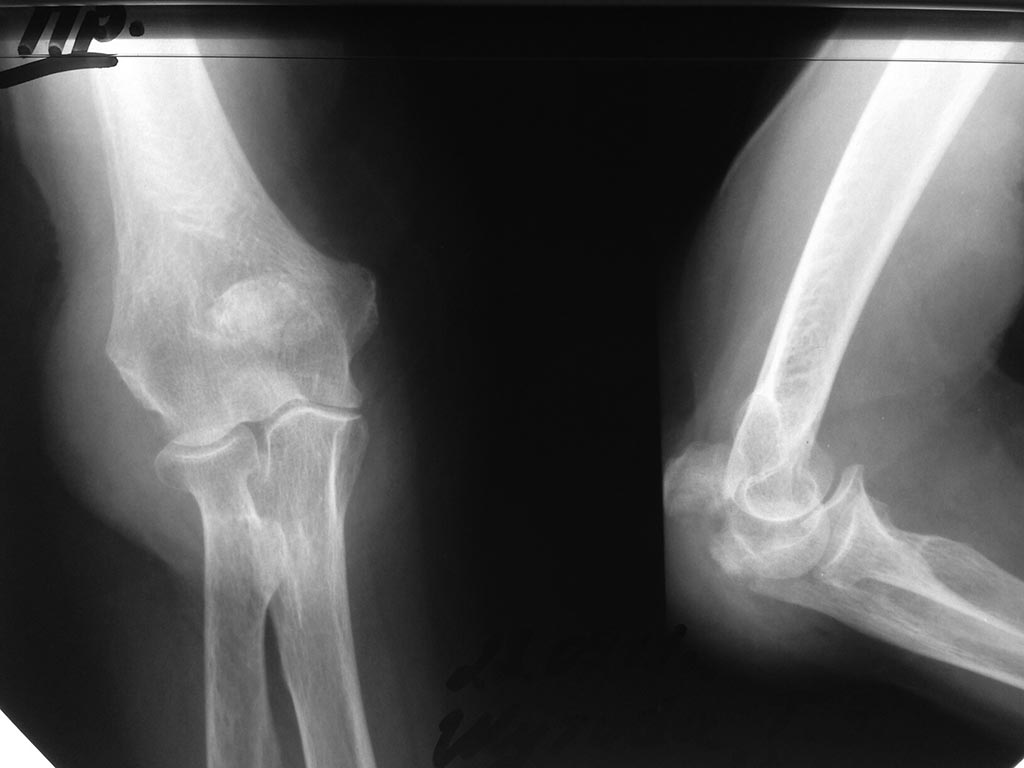

Больная 75 лет поступила с оскольчатым переломом локтевого отростка в октябре. На разборе под руководством профессора решено выполнить операцию остеосинтез локтевого отростка спицами и прволочной петлей.

В течение недели готовили к операции. Сопутствующая патология Гипертоническая болезнь 3 АД3 Сахарный диабет 2 типа. После коррекции сопутствующей патологии в операционной на вводном наркозе гипертонический криз. Больная снята со стола, в течение недели подготовка к операции терапевтом. Повторно спустя 2 недели

после травмы пациетка взята в операционную. Под ЭТН проведена операция остеосинтез локтевого

отростка спицами и проволочной петлей. Заживление первичным натяжением. ЛФК сустава не назначалось.

Перед выпиской по моему настоянию сделаны рентгенограммы. Больная выписана, и профессор утверждает что все в пределах нормы. На протяжении месяца больная под его руководством занимается ЛФК.